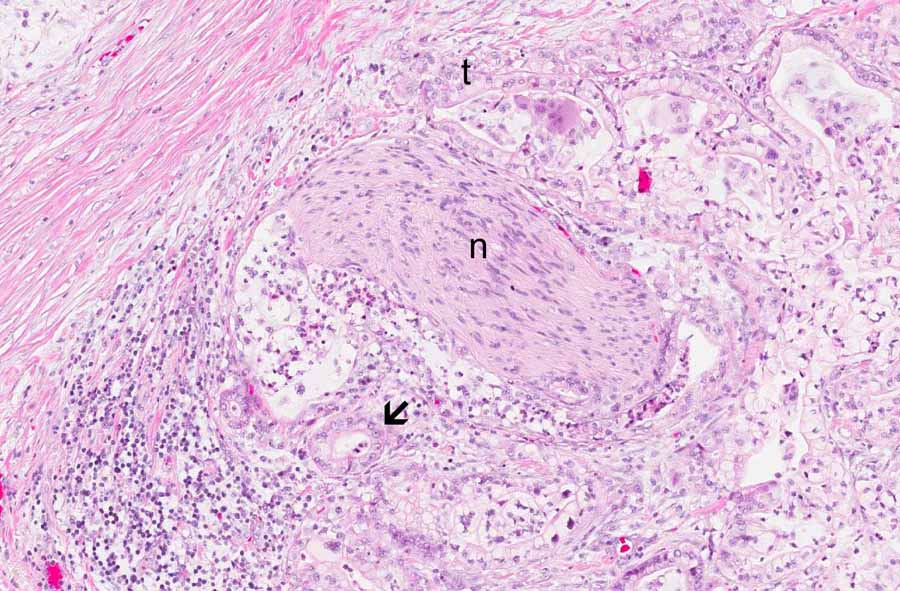

Area 3: There are large glands with hyperplastic changes and clouding of the epithelial cells accompanied by mild atypia. The level of atypia and architectural changes in these glands are most consistent with pancreatic intraepithelial neoplasm IB (PanIN IB).

Hematoxylin & eosin

• In other areas (Area 3), there are enlarged glands with proliferation of the epithelium and mild nuclear atypia. These glands are best interpreted as pancreatic intraepithelial neoplasm PanIN IB (IB). The atypical changes, the level of crowding, and architecture are not high enough for higher grades of PanIN.